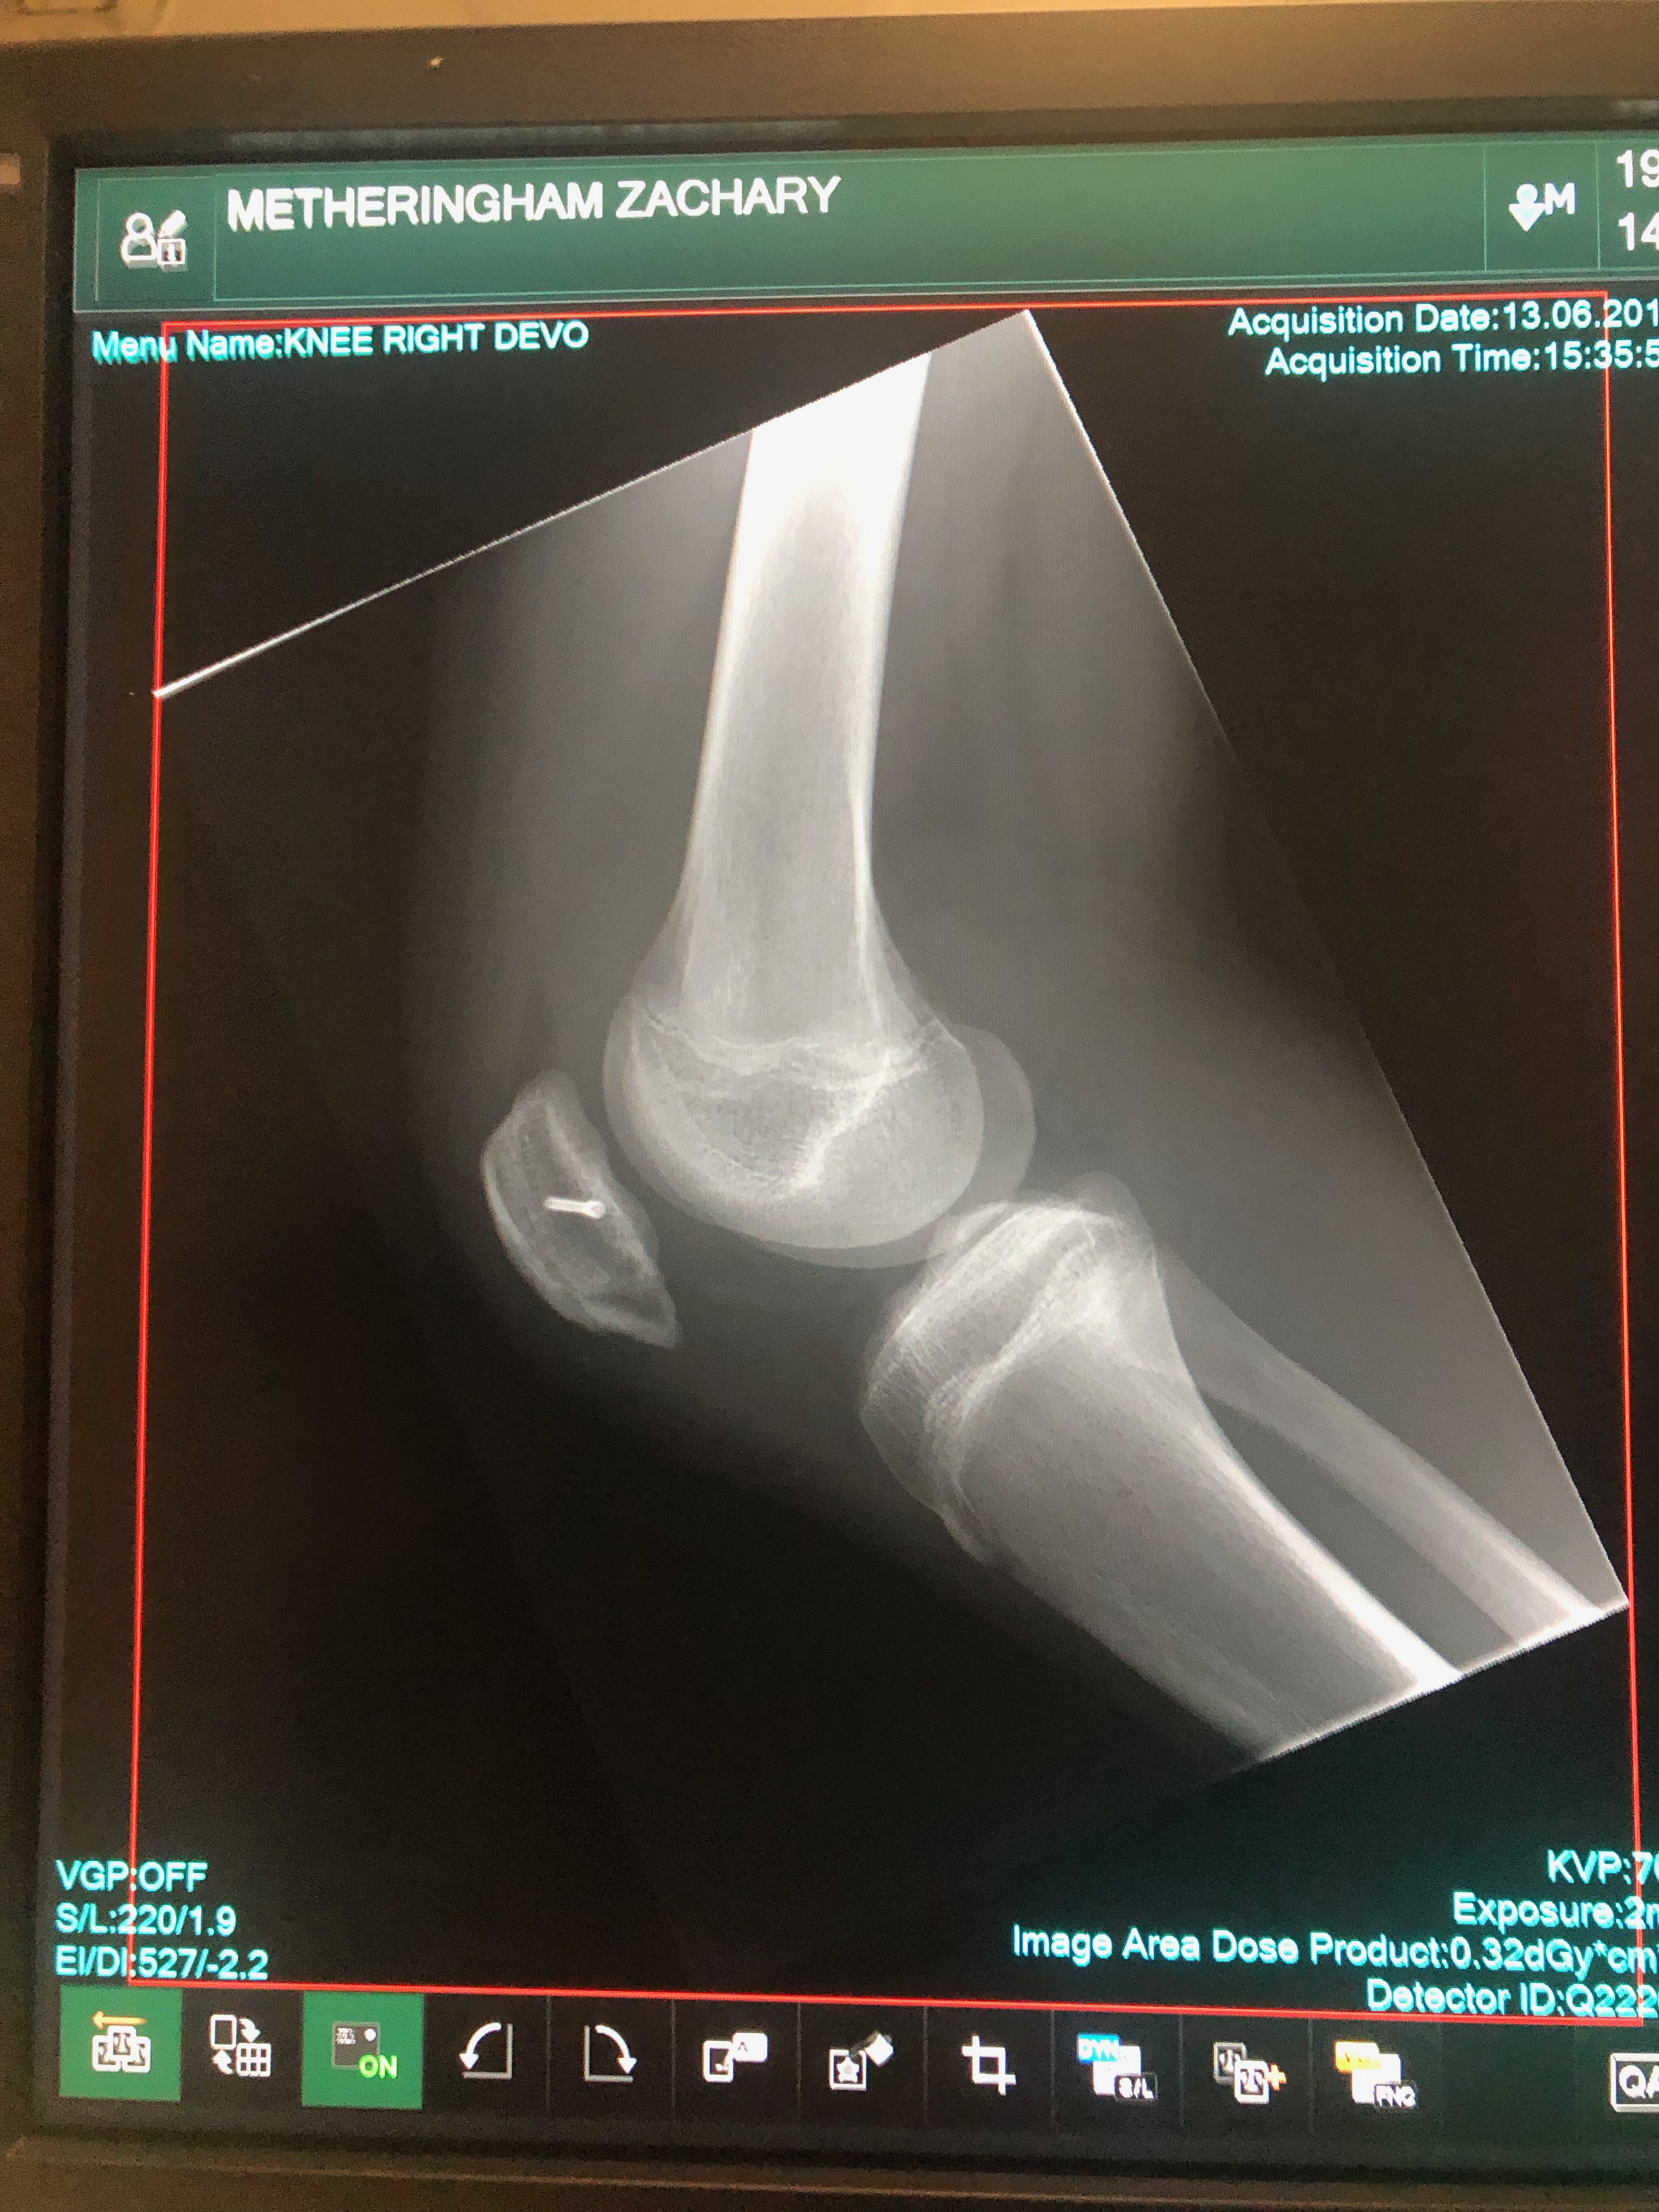

A quick video of my life over the last couple of years ! Never been an easy journey since 2016 and the knee injuries and recovery and rehabilitations, but learning and developing all the time.